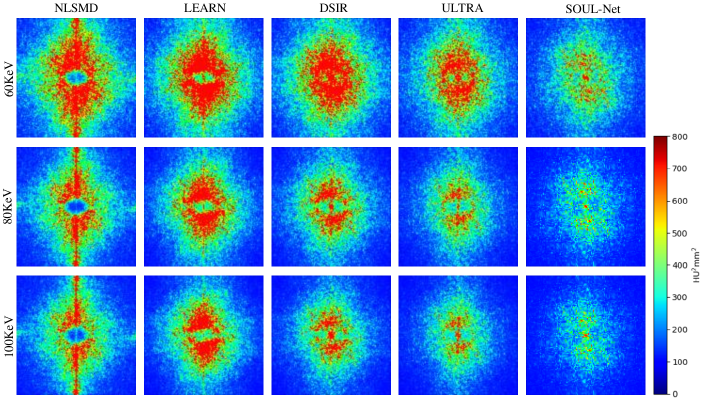

The NPS of all results are shown in Fig. 4. We can see that in both high- and low-frequency bands, the error in the results of SOUL-Net is lower than that of the other methods. This can be treated as additional evidence of the effectiveness of our proposed method.

To further analyze the noise in the results of different methods in different frequency bands, the NPS maps are drawn in Fig. 8. It is clear that the proposed SOUL-Net outperforms all other methods in noise suppression.